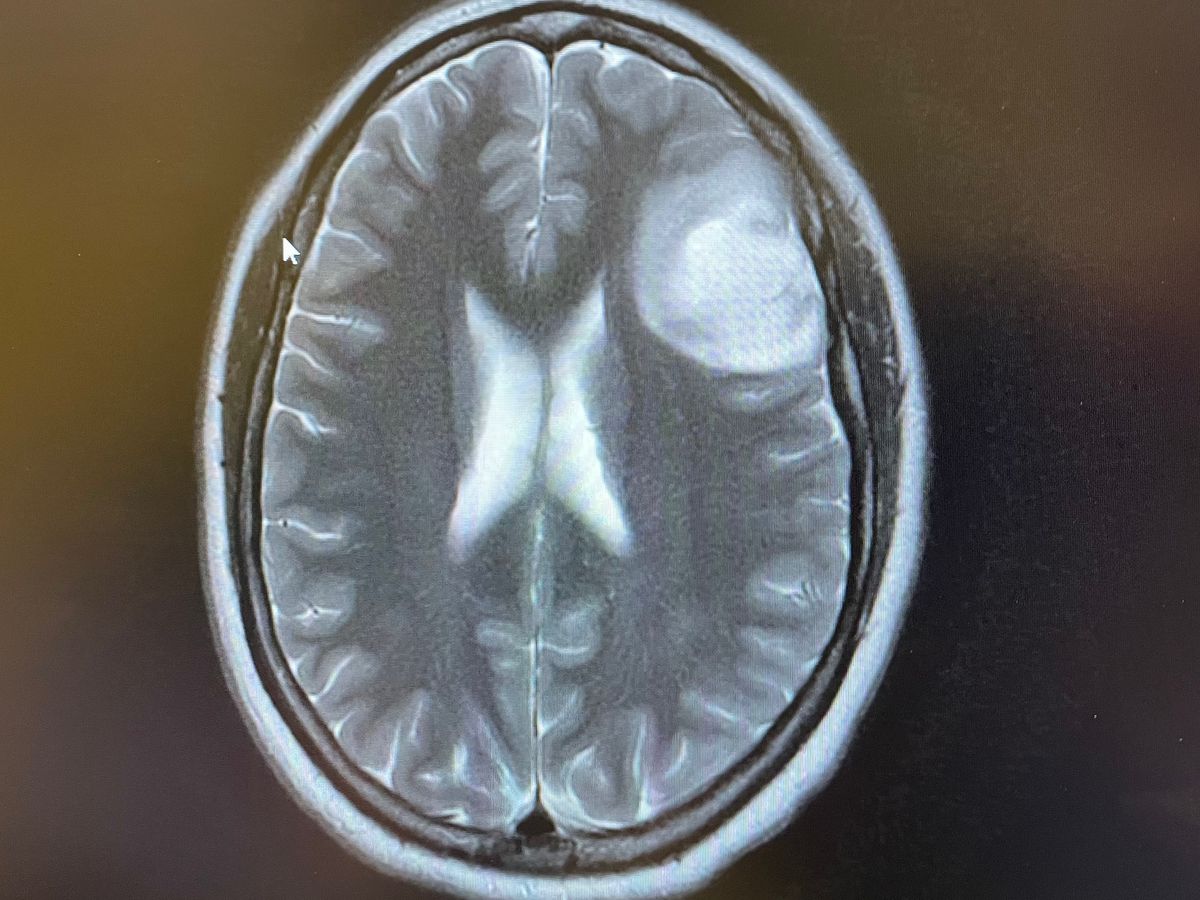

Hi, my name is Maigen and I’m starting this Gofundme for my sister-in-law, Brittanie Rangel. Brittanie just discovered she has a large mass on her brain. She will be having surgery December 29th and she, and her family, could really use all of the help and prayers they can get right now. It is not determined yet if this mass is cancerous or not. This was of course very unexpected and the brain surgery will be very tough to heal from. We are asking for any donations to help with the burden of the medical bills that are to come. Please keep Brittanie and my family in your thoughts and prayers and please share this post. Thank you so much.